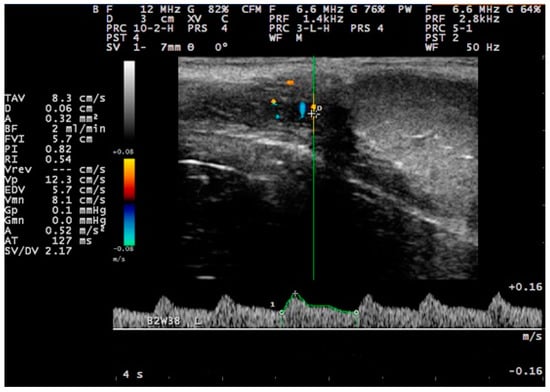

3.3. Pulsed-Wave Doppler

4.4. Proposed Segments of the Artery and Haemodynamic Parameters for Doppler Evaluation